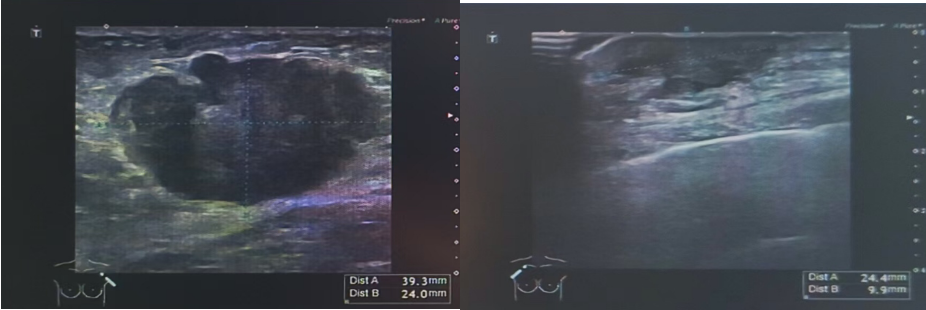

乳腺彩超(2024-7-25):

图 乳腺彩超(2024-7-25)

(左):左乳11点结节:1.27*0.65cm;(右):左侧腋窝淋巴结:2.7cm*1.3cm

右侧胸壁结节:较大者约1.22*0.30cm。

左乳11点结节:大小约1.27*0.65cm。

右侧腋下可及低回声区,范围约1.96*0.62cm。

左侧腋窝淋巴结:较大者约2.7*1.3cm。

乳腺彩超(2024-9-2):

图 乳腺彩超(2024-9-2)

(左):左乳11点结节:1.21*0.59cm;(右):左乳11点结节:1.21*0.59cm

右侧胸壁结节:较大者约1.01*0.35cm。

左乳11点结节: 大小约1.21*0.59cm。

右侧腋下可及低回声区,范围约2.01*0.54cm。

左侧腋窝淋巴结: 较大者约1.8*1.0cm。

乳腺彩超(2024-12-4):

图 乳腺彩超(2024-12-4)

左乳11点结节:0.85*0.45cm

右侧胸壁结节:较大者约0.98*0.25cm。

左乳11点结节: 大小约0.85*0.45cm。

右侧腋下可及低回声区,范围约2.2*0.5cm。

左侧腋窝淋巴结: 较大者约1.4*0.5cm。